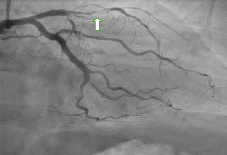

Suicide is an important cause of mortality among adults. Suicidal hanging attempts are associated with various adverse cardiovascular outcomes.